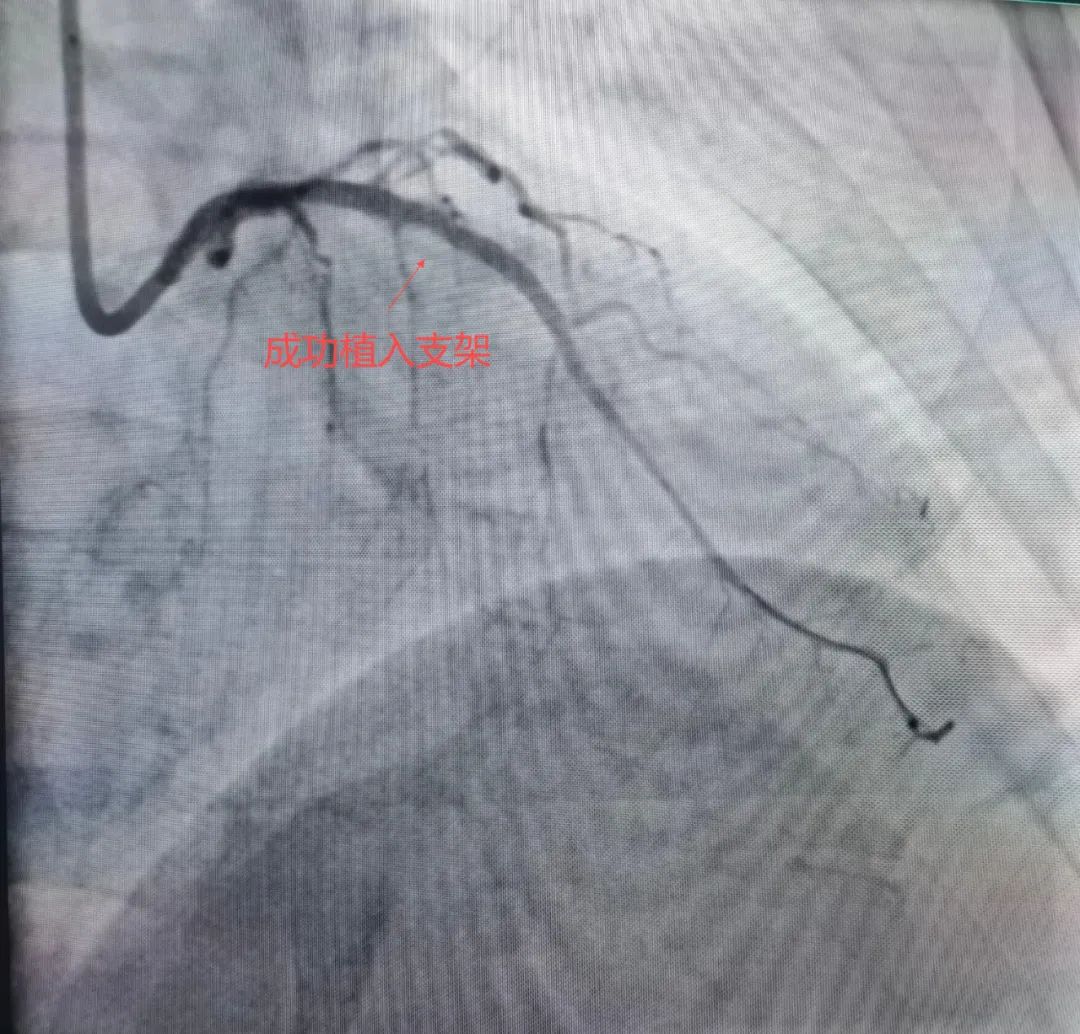

针对赵大爷的复杂病情,团队进行了充分术前讨论,决定采用“冠状动脉旋磨+冲击波球囊”的组合方案,最终成功置入支架,整个手术过程顺利,免除了患者外科开胸搭桥的痛苦。

冠状动脉钙化是老年冠心病患者的常见难题,重度钙化病变的介入治疗曾是临床“禁区”。旋磨术通过物理磨削打破钙化屏障,冲击波球囊则利用声波能量实现钙化斑块的高效碎裂,两者联合可显著提高手术成功率,减少血管损伤风险。该病例的成功实施,为高龄、高危冠心病患者带来了更安全有效的治疗选择。